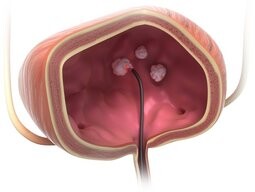

W jaki sposób skutecznie usuwamy laserowo raka pęcherza?